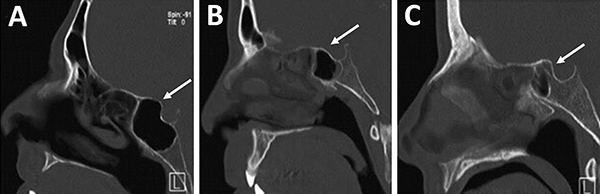

Al observar el seno esfenoidal debemos tener en cuenta la presencia de tabiques internos. Estos no deben ser tomados como referencia de línea media por su variabilidad. En este sentido, un dato cardinal es que un 90% los mismos se dirigen a las carótidas (fig. 13).1,15,23

La distancia intercarotidea determina el campo quirúrgico; a menor distancia es menor el campo y mayor el riesgo de lesión iatrogénica vascular. Otro punto a tener en cuenta es la presencia o no de cobertura ósea de la misma. En algunas oportunidades se va a encontrar recubierta por una lámina de hueso y, en otras, desprovista de la misma (fig. 13).15,23

Figura 13: Relación carótida – septaciones esfenoidales en TC cortes axiales. A) Septum interesfenoidal se inserta sobre meso carotídeo izquierdo (flecha blanca); B) Septaciones incompletas que se insertan sobre meso carotídeo en ambos senos esfenoidales (flechas blancas).

Figura 14: Localización de nervio óptico en TC cortes coronales. A) Nervio óptico dehiscente; B) Nervio óptico en su meso, con variante hiperneumatizada esfenoidal.